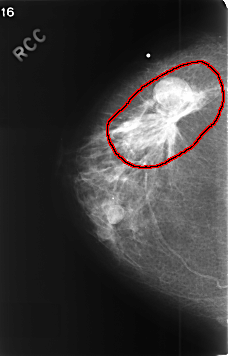

C_0457_1.RIGHT_CC

FILE: C_0457_1.RIGHT_CC.OVERLAY

TOTAL_ABNORMALITIES 1

ABNORMALITY 1

LESION_TYPE MASS SHAPE IRREGULAR MARGINS SPICULATED

ASSESSMENT 5

SUBTLETY 5

PATHOLOGY MALIGNANT

TOTAL_OUTLINES 2

BOUNDARY